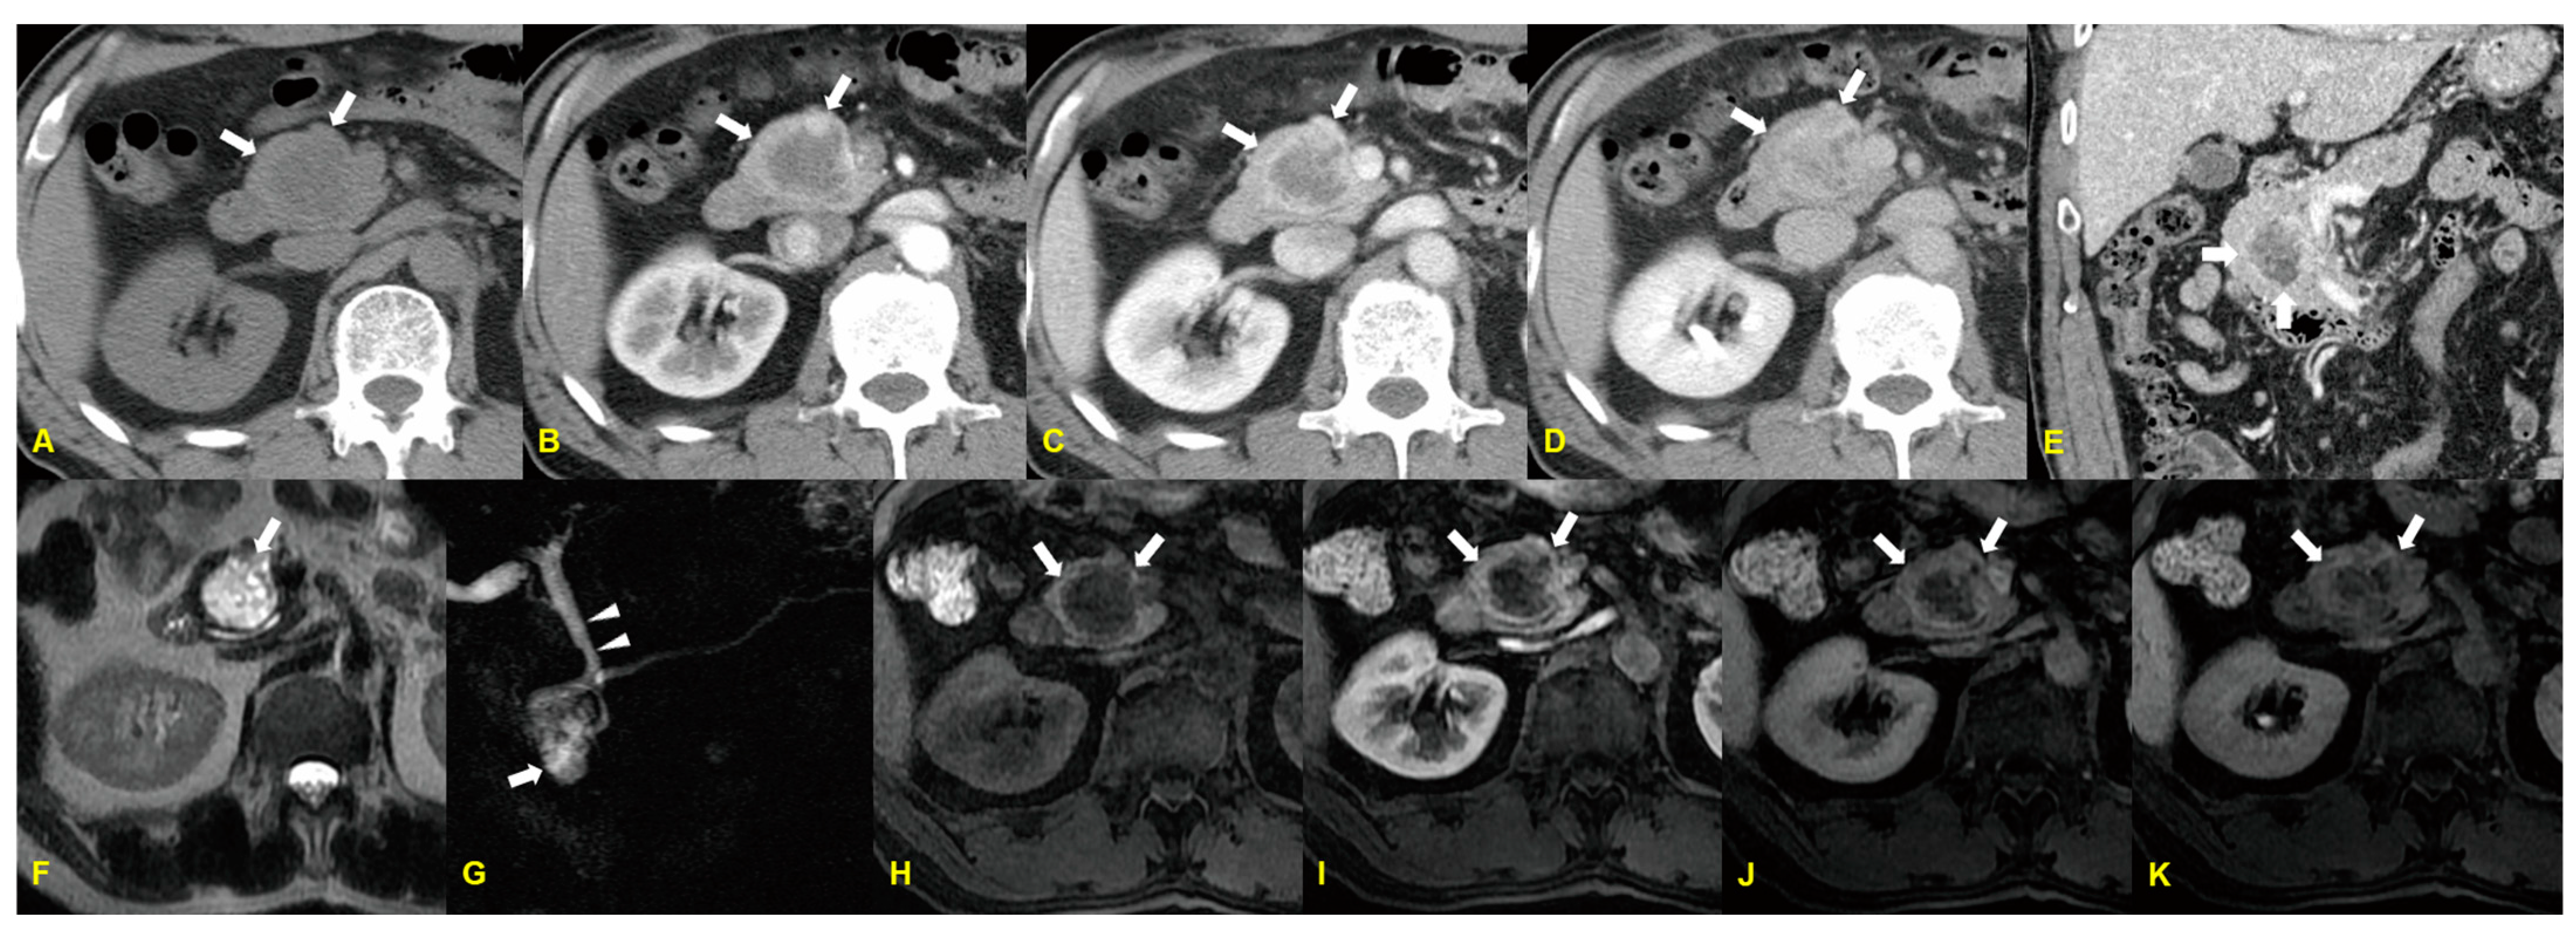

3. Acinar Cell Carcinoma

3.1. Imaging Finding

3.2. Differential Diagnosis

| Acinar cell carcinoma | Solitary/Exophytic and hypovascular mass with well-defined margin/Calcifications (frequent) |